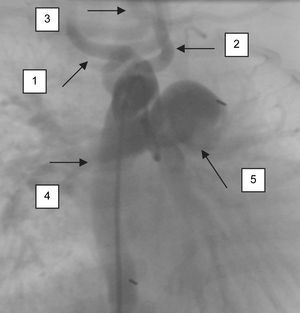

Una niña de 7 meses de edad se presentó con antecedentes de soplo cardíaco detectado durante su ingreso hospitalario a causa de una neumonía. Había sido visitada en un centro médico terciario con un cuadro de sudación, fatiga, disnea y cianosis, al igual que antecedentes de infecciones respiratorias frecuentes. Mediante ecocardiografía se estableció el diagnóstico de conducto arterioso permeable y coartación de aorta. En la exploración física, el peso de la paciente se encontraba por debajo del percentil 25, la frecuencia cardíaca era de 150 latidos por minuto, presión arterial de 100/45 mmHg en el brazo derecho y de 90/40 mmHg en la pierna derecha. Los pulsos femorales eran débiles. La exploración cardíaca reveló un soplo continuo en el borde esternal superior izquierdo. En los estudios de laboratorio destacó un valor de hemoglobina de 8,8g/dl. El electrocardiograma demostró una desviación del eje a la izquierda. En la radiografía de tórax se observó un aumento de la vascularidad pulmonar y un cono pulmonar prominente. El índice cardiotorácico era de 0,062. La ecocardiografía demostró un conducto arterioso permeable con hipertensión pulmonar. La angiografía también demostró un cayado aórtico derecho con troncos comunes de la arteria tanto subclavia como vertebral (figs. 1-3).

En condiciones normales, la arteria vertebral se origina como primera rama de la arteria subclavia. Sus anomalías son excepcionales y son más frecuentes en el lado izquierdo. Previamente se han descrito diversos orígenes anómalos de estas arterias: 1) arteria vertebral izquierda originada a partir del cayado aórtico distal después de la arteria subclavia izquierda, 2) arteria vertebral izquierda originada como tronco común con la arteria tirocervical, 3) arteria vertebral izquierda originada como tronco común con la arteria subclavia izquierda, 4) arteria vertebral derecha originada a partir del tronco tirocervical, 5) arteria vertebral derecha originada a partir de la arteria carótida común y 6) arteria vertebral derecha originada a partir de la arteria carótida externa4,5. No obstante, el tronco vertebral común y la combinación de esta anomalía con el tronco de la subclavia común no se habían descrito previamente.